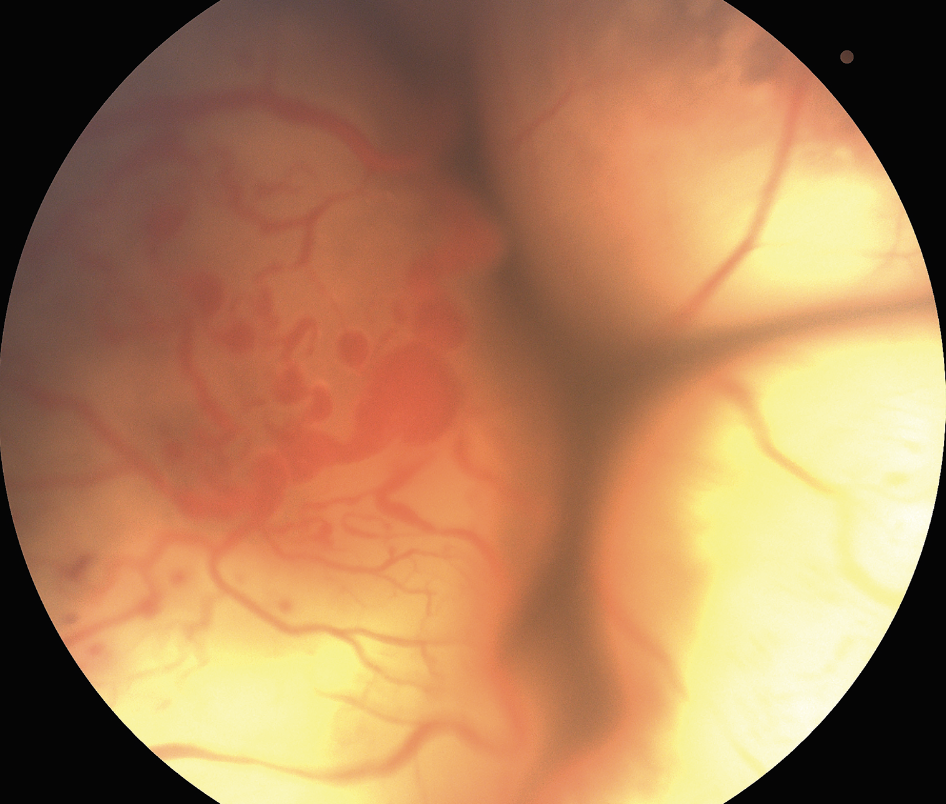

![]() |

| Figure 2. Total exudative retinal detachment from Coats’ disease. Note the extensive subretinal yellow exudates and the numerous vascular abnormalities include light bulb aneurysms. Anterior chamber infusion with external drainage was performed with subsequent perfluorooctane injection and endolaser treatment. |